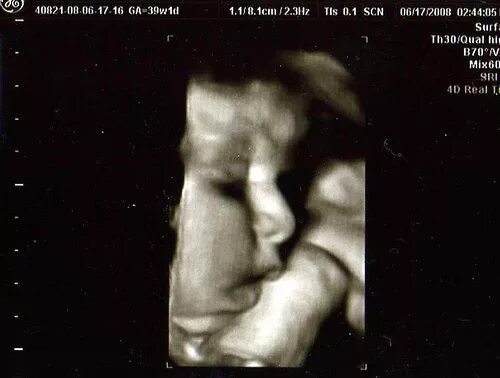

39 недель 2 дня